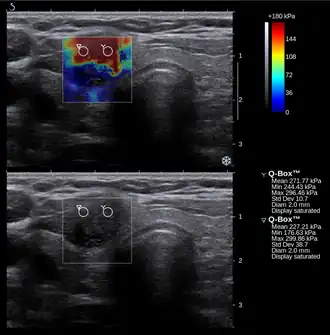

![]() Conventional ultrasonography (lower image) and elastography (supersonic shear imaging; upper image) of papillary thyroid carcinoma, a malignant cancer. The cancer (red) is much stiffer than the healthy tissue. | |

Elastography is any of a class of medical imaging diagnostic methods that map the elastic properties and stiffness of soft tissue.[1][2] The main idea is that whether the tissue is hard or soft will give diagnostic information about the presence or status of disease. For example, cancerous tumours will often be harder than the surrounding tissue, and diseased livers are stiffer than healthy ones.[1][2][3][4]

Supersonic shear imaging (SSI)

Supersonic shear imaging (SSI)[8][9] gives a quantitative, real-time two-dimensional map of tissue stiffness. SSI is based on SWEI: it uses acoustic radiation force to induce a 'push' inside the tissue of interest generating shear waves and the tissue's stiffness is computed from how fast the resulting shear wave travels through the tissue. Local tissue velocity maps are obtained with a conventional speckle tracking technique and provide a full movie of the shear wave propagation through the tissue. There are two principal innovations implemented in SSI. First, by using many near-simultaneous pushes, SSI creates a source of shear waves which is moved through the medium at a supersonic speed. Second, the generated shear wave is visualized by using ultrafast imaging technique. Using inversion algorithms, the shear elasticity of medium is mapped quantitatively from the wave propagation movie. SSI is the first ultrasonic imaging technology able to reach more than 10,000 frames per second of deep-seated organs. SSI provides a set of quantitative and in vivo parameters describing the tissue mechanical properties: Young's modulus, viscosity, anisotropy.

This approach demonstrated clinical benefit in breast, thyroid, liver, prostate, and musculoskeletal imaging. SSI is used for breast examination with a number of high-resolution linear transducers.[10] A large multi-center breast imaging study has demonstrated both reproducibility[11] and significant improvement in the classification[12] of breast lesions when shear wave elastography images are added to the interpretation of standard B-mode and Color mode ultrasound images.